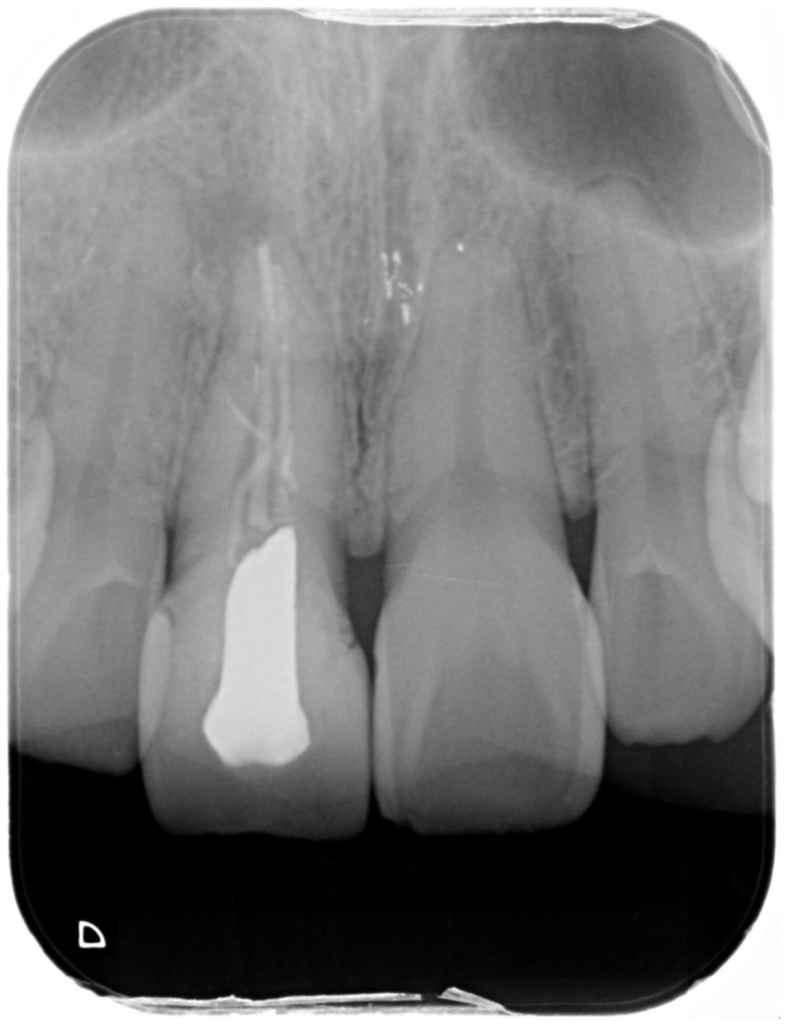

根っこの治療(根管治療の再治療)を行いました【保険診療】

今回は、左下の奥歯の根管治療(根っこの治療)の再治療を行ったケースをご紹介します。 初診で来院された時点で、この…